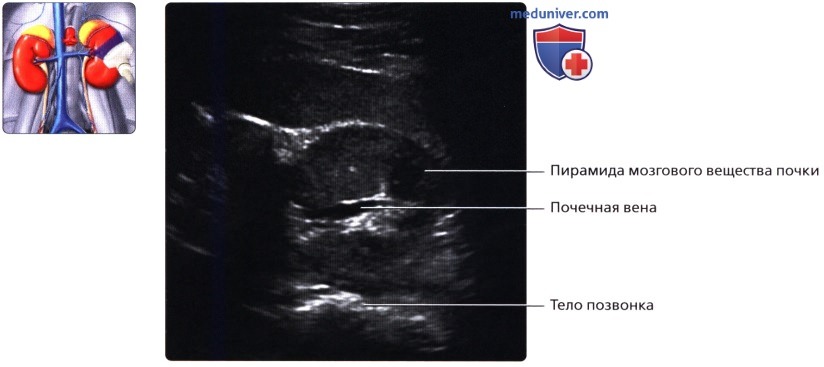

3. Внутренняя структура:

• Почки можно рассматривать как полый орган, просвет которого занят жировой тканью, почечной лоханкой, чашечками, сосудами и нервами

• Ворота почки: сюда подходят артерия и вена и выходит мочеточник

• Почечная лоханка: расширение верхнего конца мочеточника в виде воронки:

о Собирает мочу от больших чашечек (2 или 3), каждая из которых в свою очередь собирает мочу от малых чашечек (2-4)

• Почечный сосочек: точечная верхушка почечной пирамиды, содержащей собирательные трубочки, выделяющие мочу

о Каждый сосочек открывается в малую чашечку

• Корковое вещество почки: периферическая часть, содержит почечные (клубочки, сосуды), проксимальные части собирательных трубочек и петли Генле

• Мозговое вещество почки: внутренняя часть, содержит почечные пирамиды, дистальные части собирательных трубочек и петли Генле

• Кровеносные и лимфатические сосуды, нервы:

о Вена:

— Обычно по одной от каждой почки

— Лежит кпереди от почечной артерии и почечной лоханки

б) Лучевая анатомия почки:

1. Обзор:

• Забрюшинные структуры бобовидной формы с четким контуром, смещающиеся при дыхании

• Почечные вены:

о Лучше всего визуализируются при поперечном трансабдоминальном сканировании

о Также могут быть видны при сканировании в фронтальной плоскости с заднебоковой поверхности